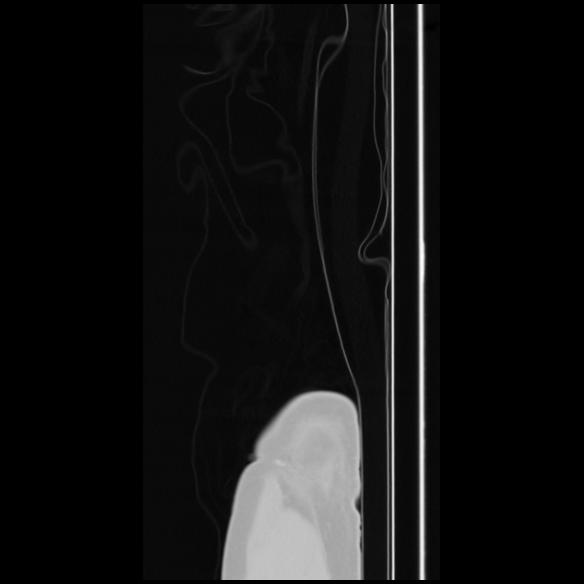

7 CUERPO,CE,Sagittal,3.000,CUERPO,Sagittal,